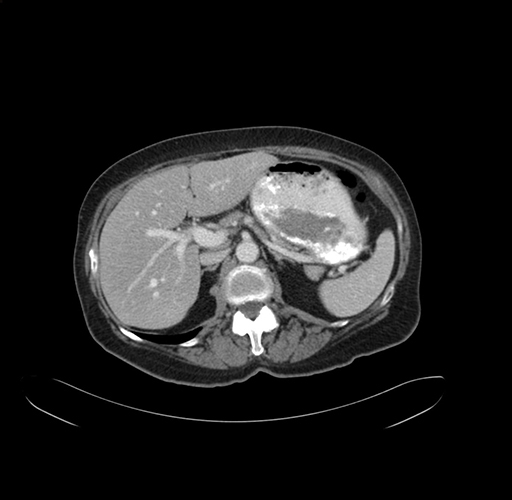

Pre-Chemo: Axial Venous